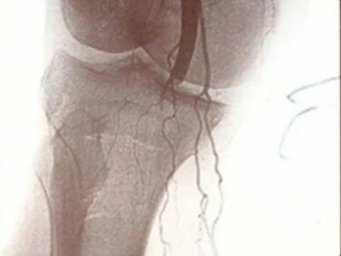

Благодаря уникальным малоинвазивным операциям по эмболизации ветвей подколенной или локтевой артерии, проведенным на современном медицинском оборудовании, пациенты могут навсегда избавиться от мучительных болей и вернуться к активной жизни.

«Эмболизация ветвей локтевой или подколенной артерии является эффективным решением для пациентов, у которых консервативное лечение не принесло желаемого результата. Эта методика часто становится единственным шансом на избавление от болевого синдрома при медиальном эпиконделите, гонартрозе 3 степени и других серьезных заболеваниях костно-двигательной системы», — поясняет врач травматолог-ортопед ГБУЗ «Домодедовская больница» Министерства здравоохранения Московской области Камал Меджидов.

Процедура эмболизации позволяет целенаправленно блокировать кровоснабжение пораженных участков, что существенно снижает болевой синдром и улучшает качество жизни пациентов. Также стоит отметить, что данный метод минимально инвазивен, что сокращает время восстановления и позволяет пациентам быстрее вернуться к обычной жизни.